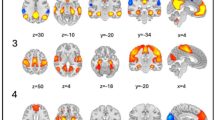

The second coactivation pattern encompassed a more extensive area within the olfactory cortex, including the posterior piriform cortex, amygdala and the entorhinal cortex. Interestingly, these regions were dissociated from higher order processing in anterior cingulate gyrus, middle frontal gyrus and supplementary motor area. There were no differences in terms of occurrences, time duration or resilience among healthy controls, PD and PV patients. A detailed presentation of the second co-activation pattern, along with its associated metrics, can be found in Fig. 2.

Spatial representation and metrics of the second co-activation pattern (CAP). (A) This brain network included the posterior piriform cortex (z = − 20, y = 0), amygdala (z = − 20) and the entorhinal cortex (z = − 20, y = 0). These regions were dissociated from higher order processing in anterior cingulate gyrus (x = − 8, x = 8), middle frontal gyrus (y = 0) and supplementary motor area (y = 0). (B) There were no differences in terms of occurrences, time duration or resilience among groups.